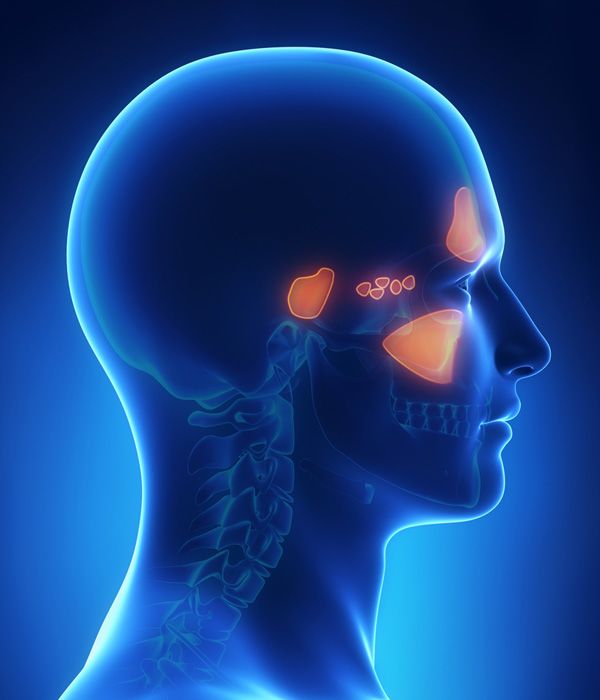

Sinus Lifts

Sinus lifts are similar to bone grafting, and our surgeons may recommend this treatment if you have lost bone volume on your upper jaw. This option will restore lost tissue and also reposition your sinus membranes. In some cases, our surgeons can eliminate the need for a sinus lift by placing zygomatic implants.